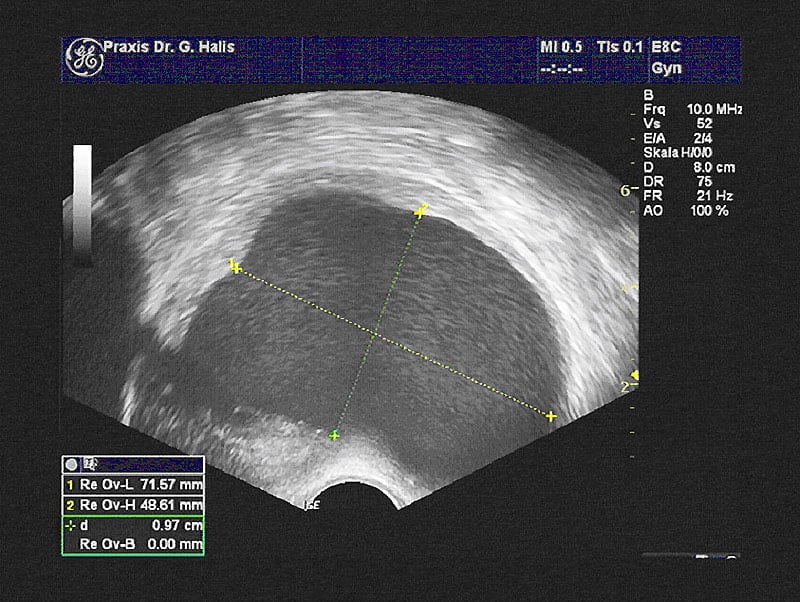

Es wäre gut, wenn Sie alle Unterlagen wie OP-Berichte, Arztbriefe, Befunde u.ä. zu dem Gespräch mitbringen könnten. Vorab senden wir Ihnen einen Patienten-Fragebogen zu, den Sie zu Hause ausfüllen und an uns mailen. Nach dem Gespräch erfolgt eine sorgfältige Tast- und Ultraschalluntersuchung.

Je nach Symptomen und Fragestellung kann auch eine Untersuchung mit anderen Verfahren sinnvoll sein, z.B. eine Darmspiegelung oder bildgebende Verfahren wie die Kernspintomographie.